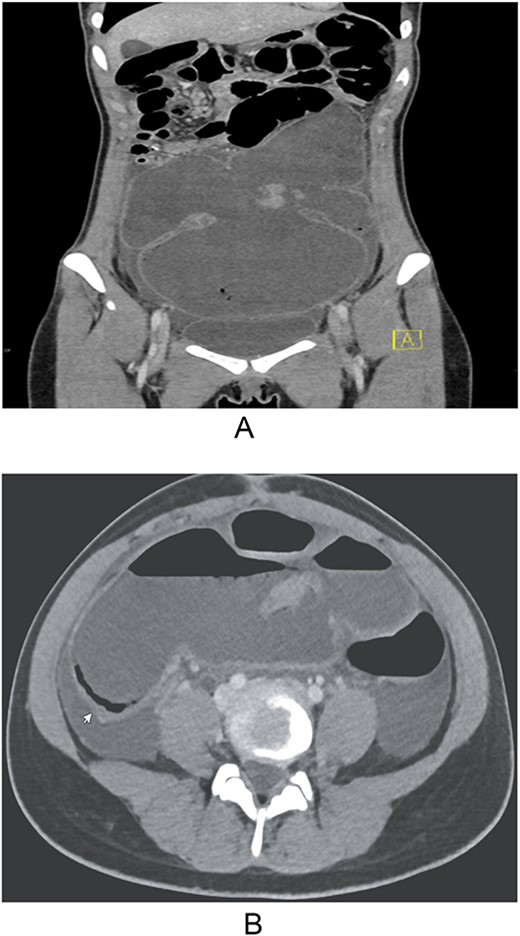

In the emergency department, she was afebrile, hypotensive, and tachycardic. Laboratory investigation was significant for leukocytosis with bandemia, hypokalemia, hyponatremia, and an elevated C-reactive protein of 229 mg/L. Computerized tomography of the abdomen and pelvis with intravenous contrast revealed dilated bowel with pneumatosis that was concerning for toxic megacolon (Fig. 1A and B).

(A and B) Computerized tomography of the abdomen and pelvis with intravenous contrast showing dilated bowel with pneumatosis mimicking toxic megacolon.